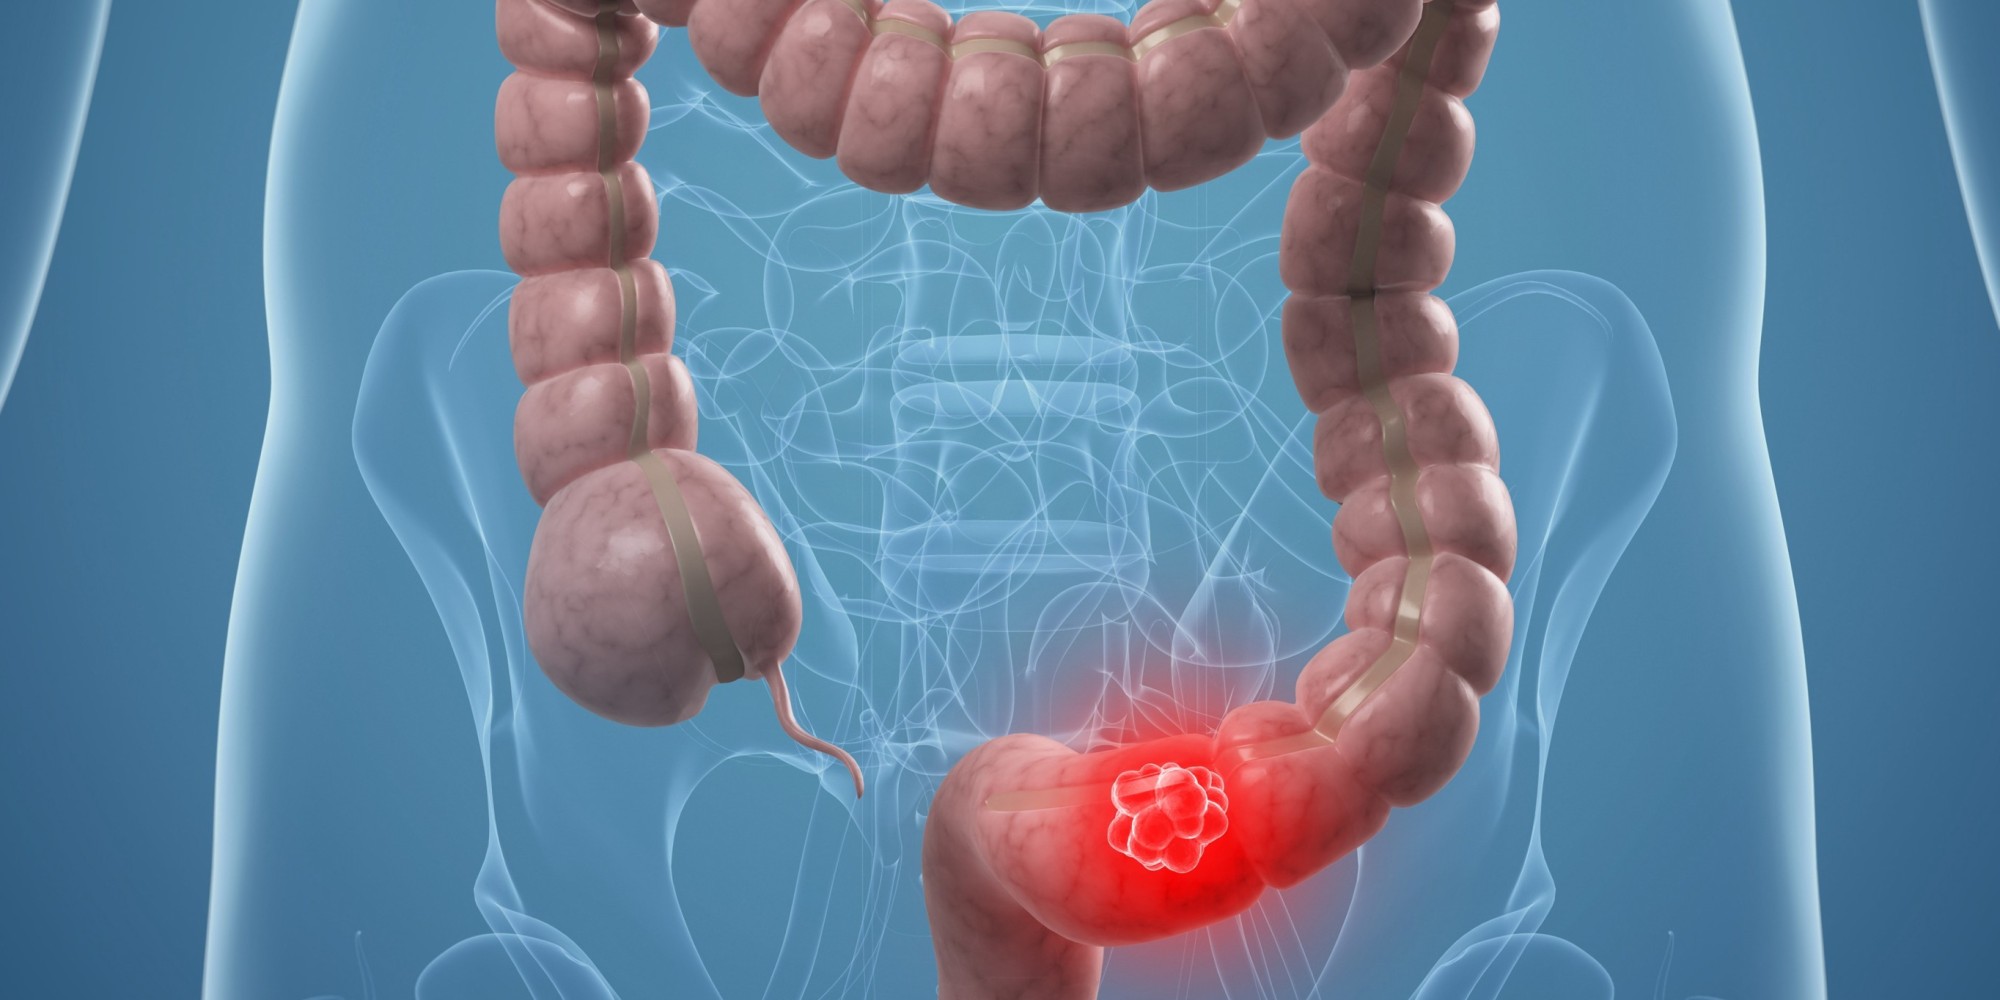

Τα ποσοστά εμφάνισης καρκίνου του εντέρου σε άτομα κάτω των 50 ετών έχουν αυξηθεί σημαντικά τα τελευταία χρόνια σε πολλές αναπτυγμένες χώρες.

Ο καρκίνος του παχέος εντέρου είναι ο τρίτος συχνότερος στον κόσμο, με 1,8 εκατομμύρια νέα διαγνωστικά περιστατικά και 881.000 θανάτους το 2018.